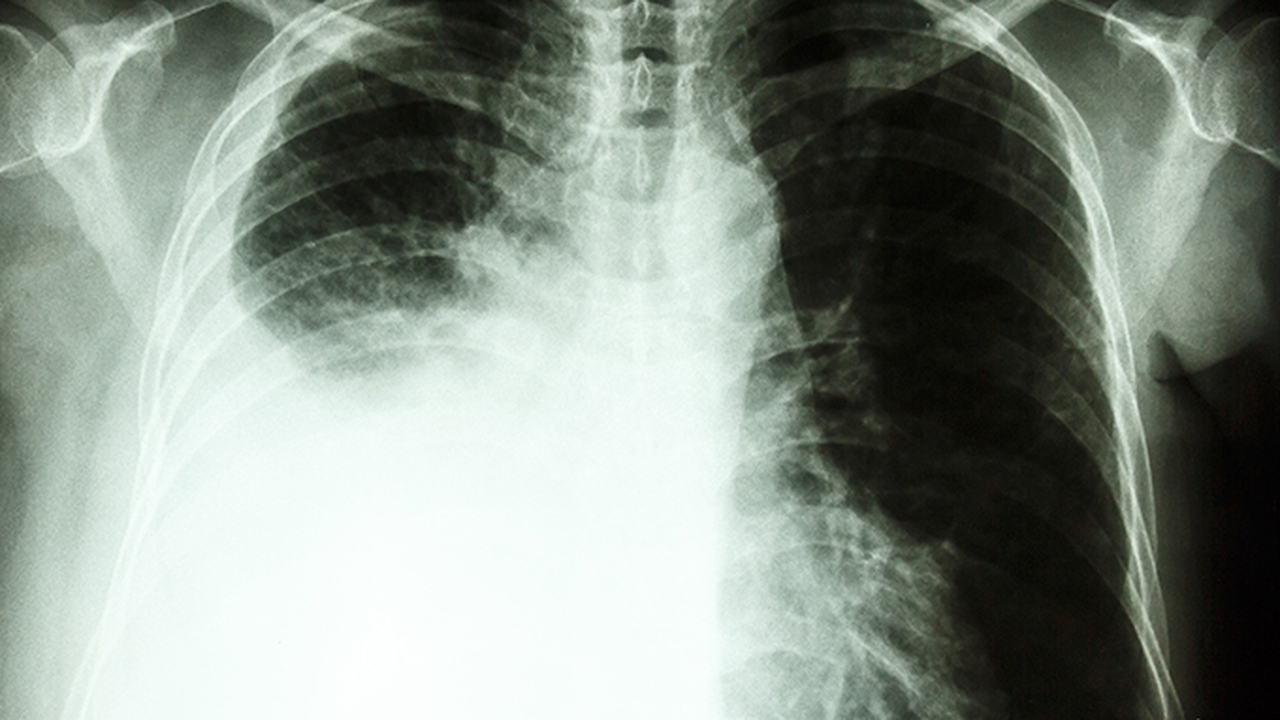

肺气肿是一种常见的慢性呼吸系统疾病,主要表现为肺泡壁破坏导致肺组织弹性减退。长期吸烟、空气污染和反复呼吸道感染是其主要诱因。早期诊断和规范治疗对延缓病情进展至关重要。